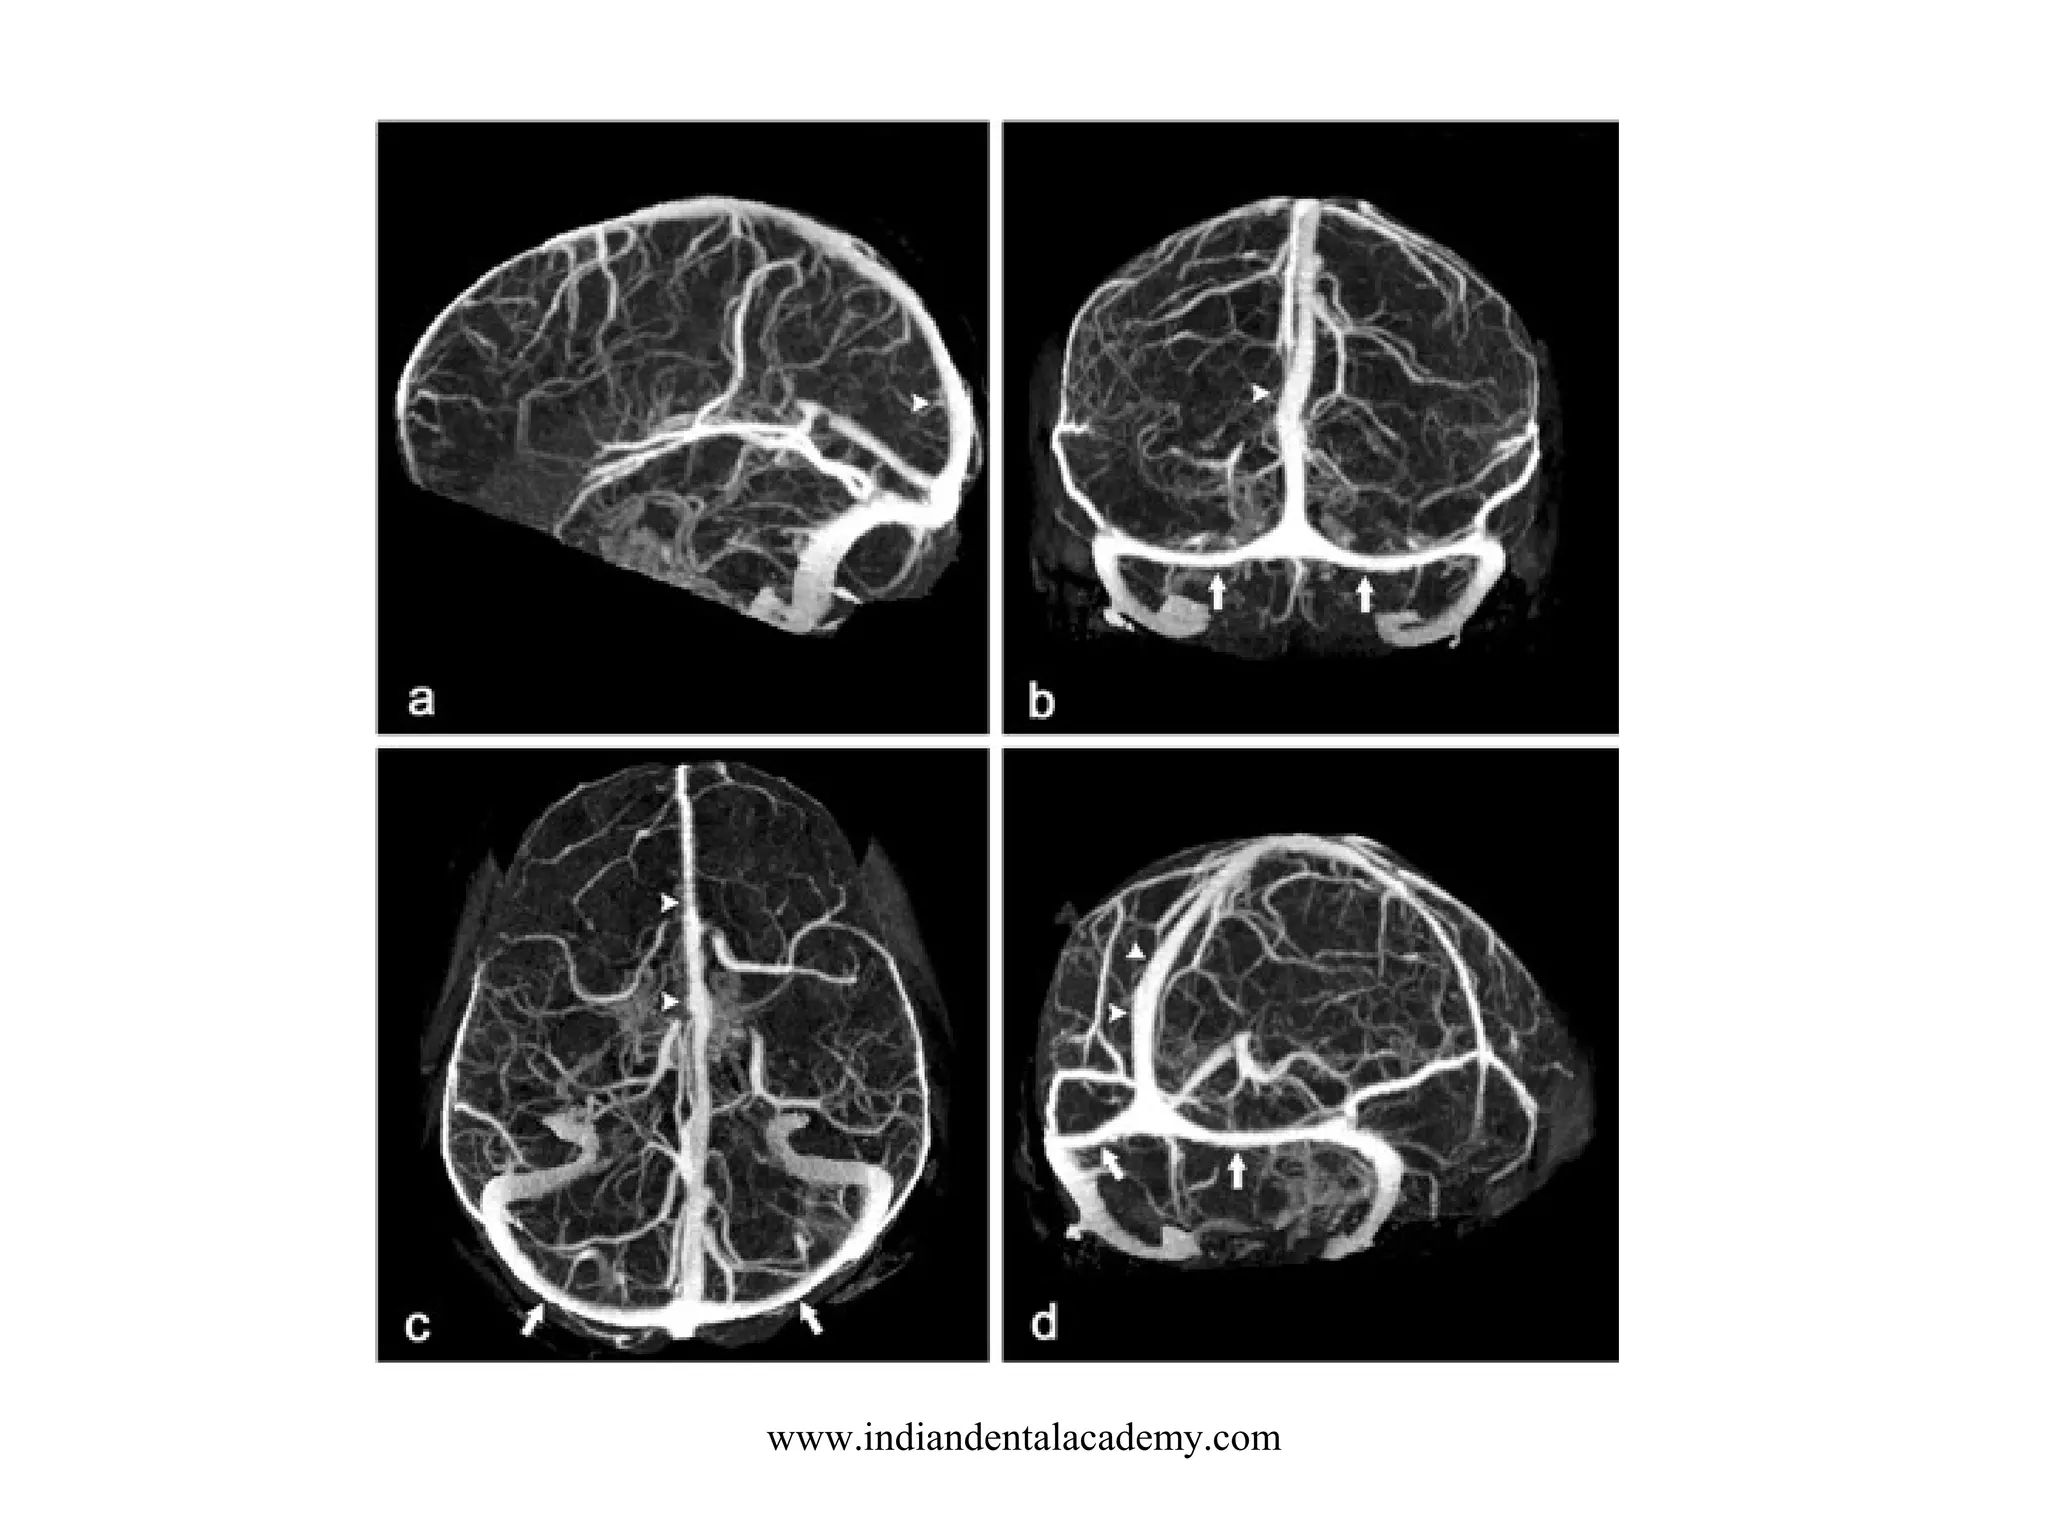

BRAIN ANGIO CTA

SCOUT: LATERAL

LANDMARK: OML

SLICE PLANE: AXIAL

I.V. CONTRAST: 100-140 ML- 3-5 ml /sec -

15 - 20 SEC DELAY CTA

30 SEC DELAY CTV

BREATH HOLD: NONE

SLICE THICKNESS: 1-2 MM

START LOCATION: BELOW SELLAR FLOOR

END LOCATION: 4-5 CM ABOVE SELLA

RECON: 50% OVERLAP

FILMING: 3 D RECON